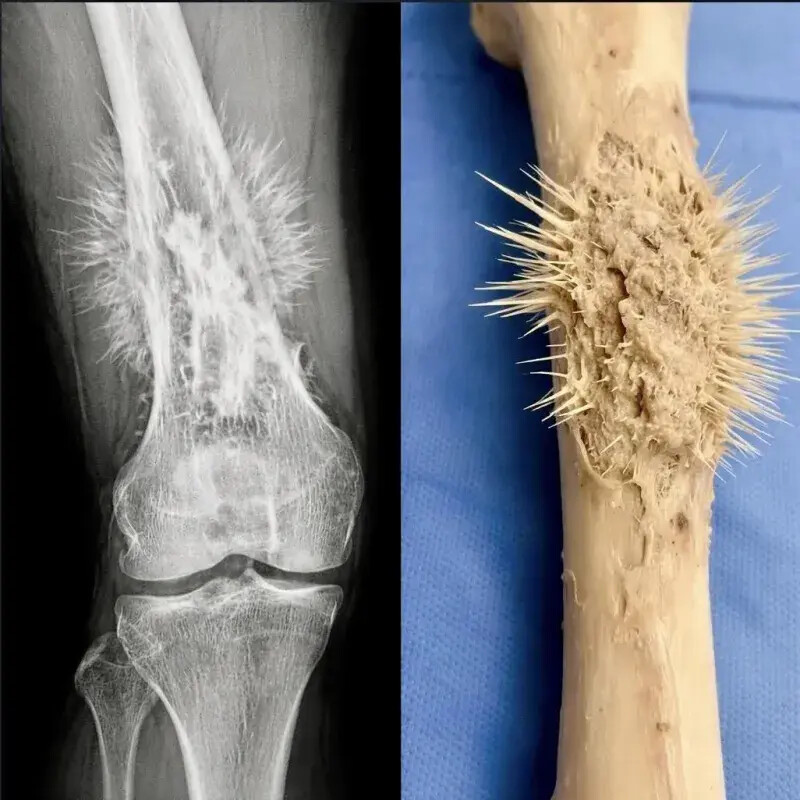

골육종 걸리면 엄청 아픈 이유.JGP